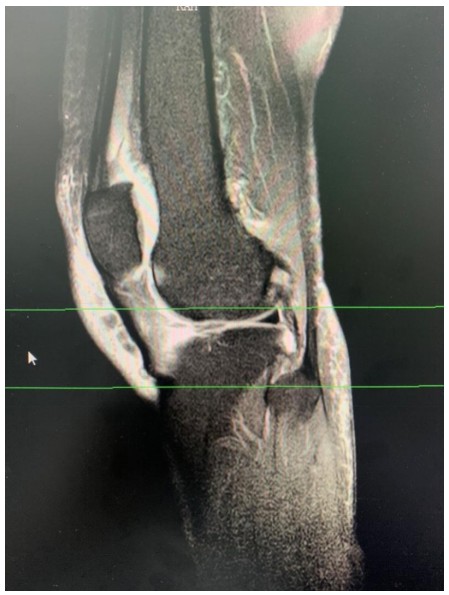

近日,衡陽市中心醫(yī)院華新院區(qū)疼痛門診接診了兩位年齡相仿、癥狀相似的女性患者,兩人都因一側膝關節(jié)腫脹、變形,疼痛難忍、下蹲受限、步行困難嚴重影響生活前來求診。兩位患者分別經過張娟、趙夢岑兩位主治醫(yī)生的診治后被診斷為膝關節(jié)退變,并且發(fā)現(xiàn)患膝側關節(jié)內存在大量積液。

膝關節(jié)炎是一種以退行性病理改變?yōu)榛A的疾患,好發(fā)于中老年人群,其癥狀多表現(xiàn)為膝關節(jié)腫痛、坐起立行時膝部酸痛不適等,偶有腫脹、彈響、積液等表現(xiàn)。如不及時治療則會導致關節(jié)畸形或殘疾。專家提醒,患有膝關節(jié)炎請及時到正規(guī)醫(yī)院就醫(yī),切莫因拖延耽誤了治療時機。